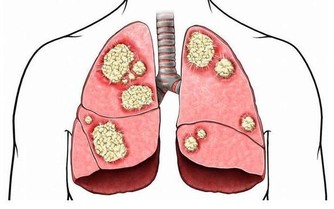

主要包括急性發作性關節炎、痛風石形成、痛風石性慢性關節炎、尿酸鹽腎病和尿酸性尿路結石,重者可出現關節殘疾和腎功能不全。

尿酸長期高,會導致肌酐高,這意味著腎臟可能出現問題,比如腎功能不全、甚至腎衰竭、尿毒症。尿酸結晶沉積導致腎小動脈和慢性間質炎症使腎損害加重。有研究顯示,尿酸可直接使腎小球入球小動脈發生微血管病變,導致慢性腎臟疾病。

高尿酸會增加腎功能降低風險21%,增加因慢性腎病死亡風險68%。